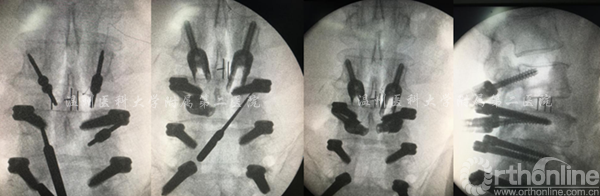

术中显露置钉的过程

术中透视资料